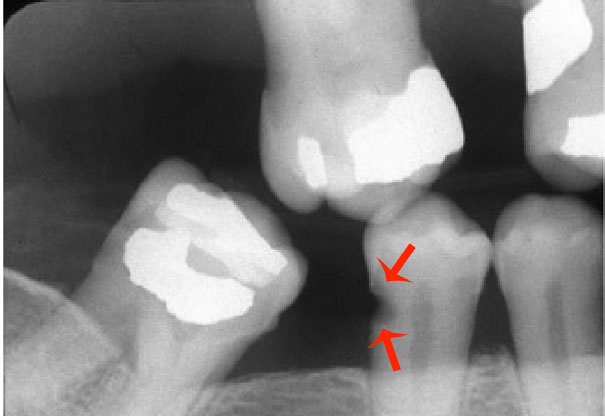

Root Surface Caries (Figure 4). A more common lesion now found clinically, due to patients keeping their teeth longer.

Root Surface Caries on the Rise

Root surface caries has increased due to the increased retention of teeth during adulthood thanks to various caries-preventive measures and patients living longer. About one-half of US adults are affected with root surface caries by age 50, with an average of about three lesions by age 70. Fluoride is very effective in preventing root surface caries. Results of studies have demonstrated that the presence of fluoridated drinking water throughout the lifetime of an individual prevents the development of root surface caries. Furthermore, it has been observed that the use of sodium fluoride (NaF) dentifrice results in a significant decrease in root surface caries of more than 65%. There has not been much data collected on professional topical applications affecting root surface caries. But in a preclinical model, all three approved topical fluorides decreased the formation of root caries by 63% to 76%.

Figure 4. Root surface caries.

Figure 4